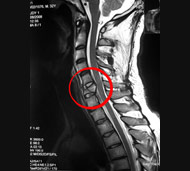

- Магнітно-резонансна томографія (МРТ). МРТ використовує магнітну силу і радіохвилі, щоб відтворити зображення, отримані через комп'ютер. Це допомагає в ситуаціях, коли необхідно розглянути спинний мозок і виявити грижу міжхребцевого диску, згустки крові і інші утворення, які можуть здавлювати спинний мозок. Але МРТ не можна проводити пацієнтам з серцевими водіями ритму або постраждалих, яким необхідна апаратура, що підтримує життєдіяльність організму чи пристосування для витягування шийного відділу хребта.

Але постановка діагнозу на цьому не припиняється. Через кілька днів після пошкодження лікар проведе неврологічне обстеження, щоб визначити ступінь важкості ушкодження і визначити ймовірну тривалість відновлення. Може знадобитися проведення додаткової рентгенографії, МРТ або інших методів обстеження.